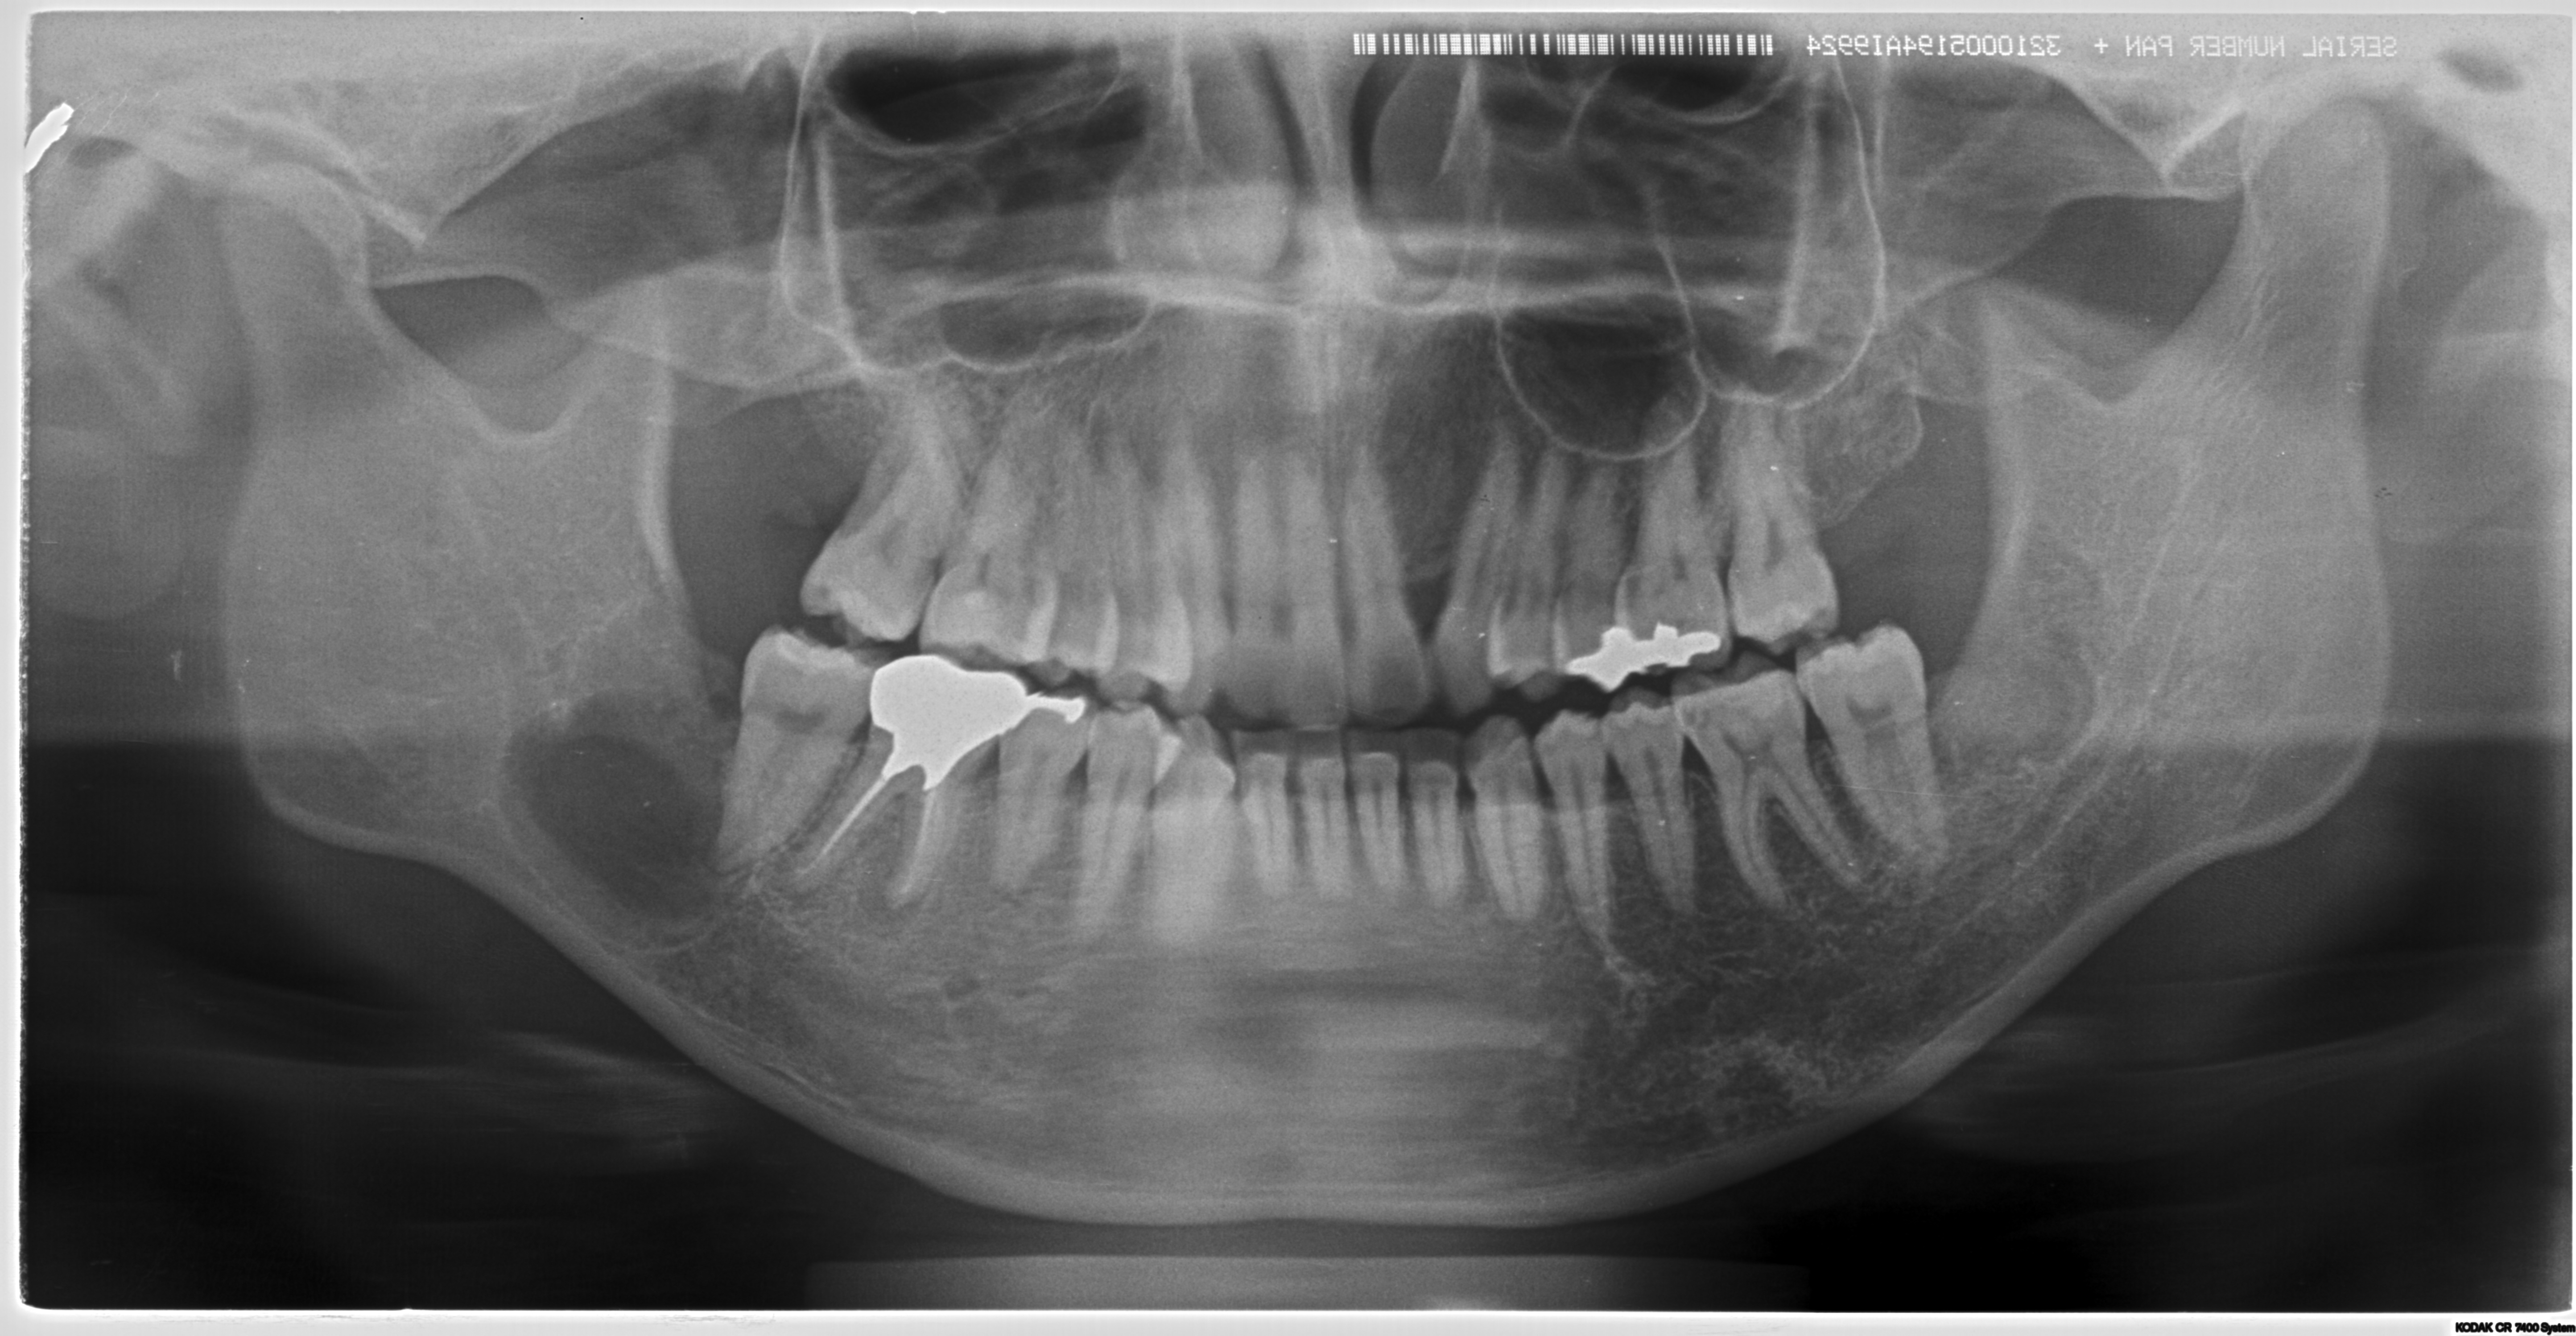

某大学病院で全身麻酔での嚢胞摘出及び右下7番の抜歯を予定されていた方の治療経過

<親知らずなどの抜歯に関して>

多くの方が経過観察になっていることが多いのが親知らずでしょう。一度腫れたりすると抜歯をしようかなと考えて歯科医院に行くケースもありますが。

完全に埋まっているケースは放置されることが多いです。(自覚症状がないため)

またそうした難抜歯は通常開業医では行わないケースが多いです。

しかし当クリニックではそうした難抜歯を積極的に行っております。

理由は簡単で症状が「歯列の乱れ」「歯周病の悪化」「口臭の原因」「手前の歯を虫歯にしてしまう」からです。

完全に埋伏しているように見えても、抜歯した時には歯茎の中にあるにもかかわらず歯石まみれの汚い状態で抜歯できるケースはザラにあります。

ご本人が気が付かないだけで、埋まっている歯ぐきから膿が常に出ている方もたくさんいらっしゃいます。(特に40代以降の方に多い)

こうした方々は常に口臭がしたり、体調によって歯茎が腫れたりしています。

他の開業医で「大学病院などでの抜歯を勧められた」などの困難症例もご相談ください。

大学病院では全身麻酔などを行い抜歯するケースも多いですが。

麻酔科医としての見解からすれば、わざわざ全身麻酔を行い(呼吸を停止させ、挿管し人工呼吸で管理することです)抜歯を行うケースは相当のリスクを伴います。

可能な限り外科処置に関しては局所麻酔で抜歯を行う事が侵襲は少ないと考えます。

そのため原則局所麻酔下(部分だけの麻酔)での抜歯を行っております。

必要な症例に関しては大学病院等に紹介をいたします。

またCTを完備しているため外科的な手術に関しては安心して受けていただけます。